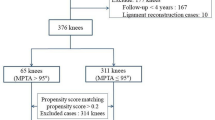

Patient selection process is depicted in Fig. 2. The baseline characteristic of included patients is presented in Table 1. Of the 180 patients included, postoperative MPTA ranges from 86.1° to 103.1° and MPTA change ranges from 1.4° to 15.3°.

After PSM, 58 pairs of patients were in groups I (postoperative MPTA < 95.0°) and II (postoperative MPTA ≥ 95.0°), and 50 pairs were in groups A (MPTA change < 8.0°) and B (MPTA change ≥ 8.0°). The covariates were matched between groups I and II (Table 2) and between groups A and B (Table 3). Comparisons of patient-reported outcome, radiological progression of osteoarthritis, and surgical failure rate between groups I and II and between groups A and B are presented in Table 4.